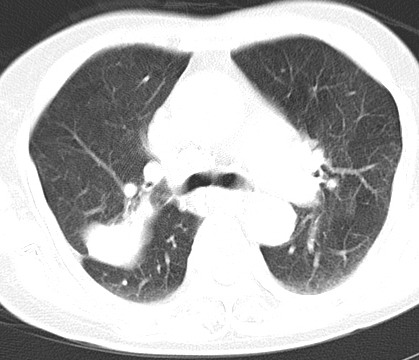

以下是引用hhcckk在2007-3-2 14:51:00的发言:[br]考虑结核球可能性大,依据[br]1病灶在下叶背段,结核的好发部位[br]2病灶内有大量的钙化,纵隔内有大量的淋巴结钙化[br]3重要的是半年前与现在相比无变化,假如是肿瘤的话不会这么‘善良’[br]4病灶周围卫星灶不明显,病灶有毛刺,胸膜凹陷,肿瘤不能完全排除,有条件的话最好做个活检

以下是引用liuyue在2007-3-2 17:15:00的发言:[br]1位置:右上叶后段[br]2性质:大分叶、粗长毛刺、条状斑片状钙化、纵隔多发淋巴结钙化,无强化,故考虑:肺结核灶(陈旧)